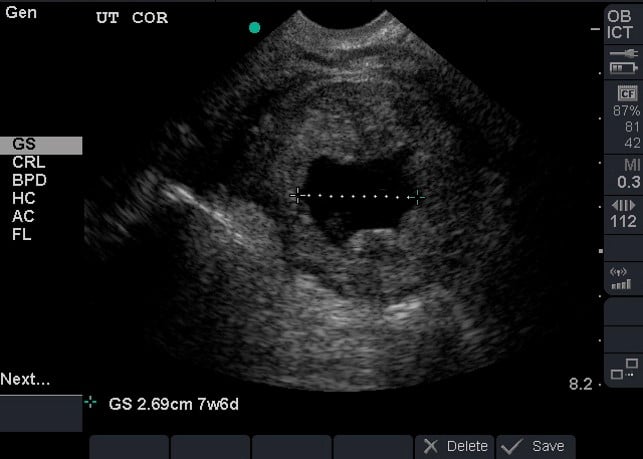

- Dating can be achieved by obtaining crown rump length when fetal pole becomes visible and then biparietal diameter when fetal skull becomes evident at the end of the first trimester.1 (Illustration 10, 11)

- Illustration 10. Transabdominal transverse view of 10-week fetus with crown rump length measurement.

- Illustration 11. Transabdominal transverse view of 15-week fetus with biparietal diameter measurement from leading outer skull (most near field) to inner skull (far field) at the level of the ventricles.